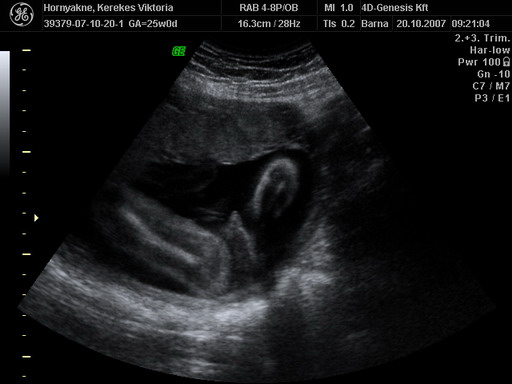

A tegnapi 4D-n már megmutatta magát ez a kis cukorfalat. Majd teszek fel képeket.

Várjuk a képeket a 4D-ről. A szerdai doki vizsgálaton mindent rendben találta: méhszáj teljesen zárt, viszont a folyásra felírt hüvelykúpot. A pénteki vidéki 4D sajna megint nem sikerült olyan jól, megint úgy feküdt, viszont ott is minden rendben volt: néztek köldökzsinór áramlást és az is teljesen OKÉ volt. :lol:

A kép amit fényképezett a doki nagyon homályos lett, így sajna csak a múltkori képeim vannak fenn, szerintem ezeket már feltettem (mármint a linket), de azért ide is becsatolom:

Kép